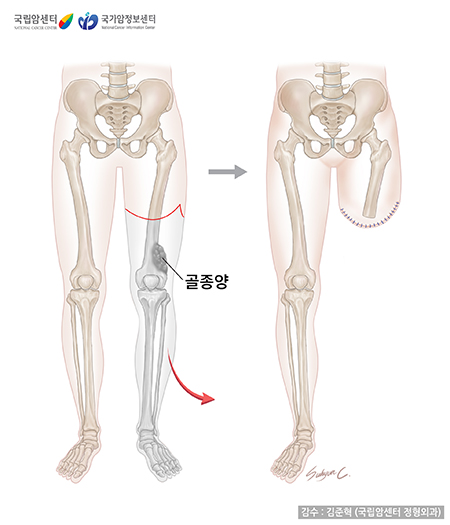

수술 방법도 과거에는 절단술 내지는 관절 이단술(관절에서 절단 또는 분리하는 것) 등이 주를 이루었으나 최근에는 극히 제한된 경우에만 이러한 수술이 시행되며 대부분의 경우 사지의 기능을 보존하면서 종양을 적출하는 사지 구제술(보존술)의 비율이 80-90% 이상을 차지하며 보편화되는 추세입니다.

사지 구제술(사지 보존술)이란 종양이 있는 다리나 팔을 절단하지 않고 치료한다는 의미입니다. 기존의 절단술과 달리 종양으로부터 충분한 절제연을 가지도록 광범위 절제술을 시행한 뒤 각종 재건 방법을 이용하여 절제술로 소실된 뼈와 연부 조직을 재건해줌으로써 사지를 보존하는 수술 방법입니다. 무엇보다 중요한 것은 종양을 완전히 절제하는 것이며, 이것이 이루어지지 않으면 어떤 방법의 재건술을 하더라도 좋은 예후를 기대하기 어렵습니다. 최근에는 수술 기법 및 항암화학요법의 발달로 절단술보다는 사지 구제술(사지 보존술)로 치료하는 추세이며 약 90% 이상의 환자에게 시행되고 있습니다.